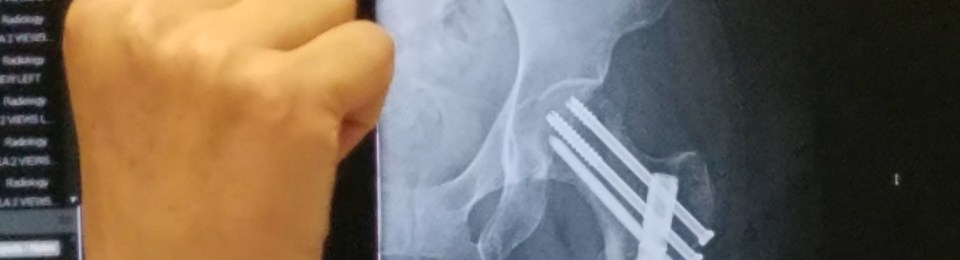

In 2007 when I fractured my pelvis, I was braver, perhaps because the damage wasn’t as grave. Yes, my pelvis was broken in four places, but the bones were cracked, rather than dislocated.

At the top of my femur are three huge screws and running the length of the femur is a rod, secured with a couple of pins. I’m confident with the repair of my femur.